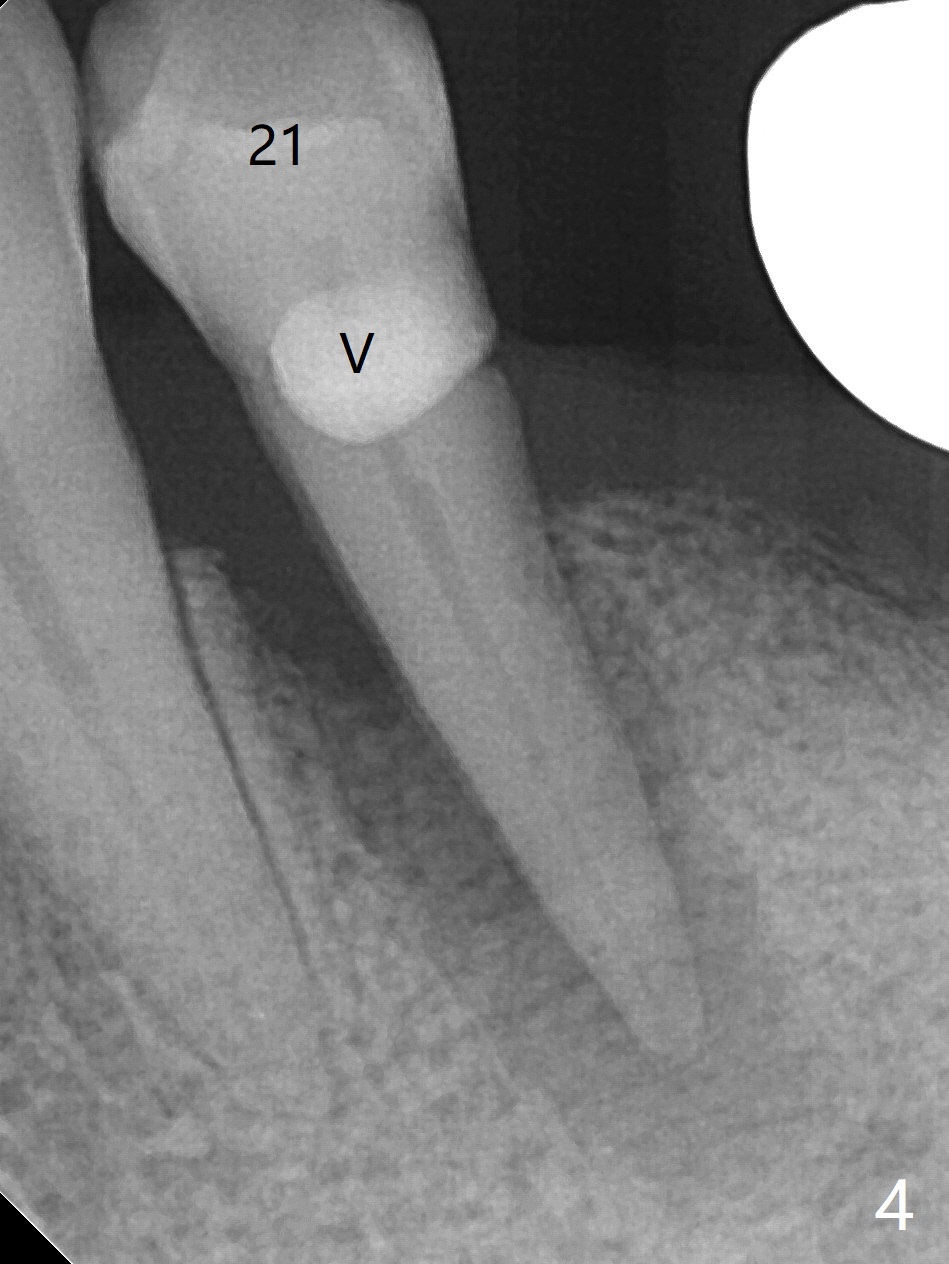

A 73-year-old man with history of stroke presented to office with #20 chewing pain 2 years ago (Fig.1). When he returns today, the tooth #20 has lost, while #21 has mobility (Fig.2), torus mandibularis (Fig.3 *) and severe bone loss, as related to Class V defect (Fig.4). As expected, the buccal plate is lost, the buccal gingiva blanching and bulging due to a curette underneath (Fig.5 *). After placement of allograft in the socket (Fig.6,8 *), a 8x8 mm BioXclude and 4-0 PGA suture are used to close the socket (Fig.7). Periodontal dressing stays in place 10 days postop (Fig.9). The patient is pleased with hemostasis. He is going to return his home state.